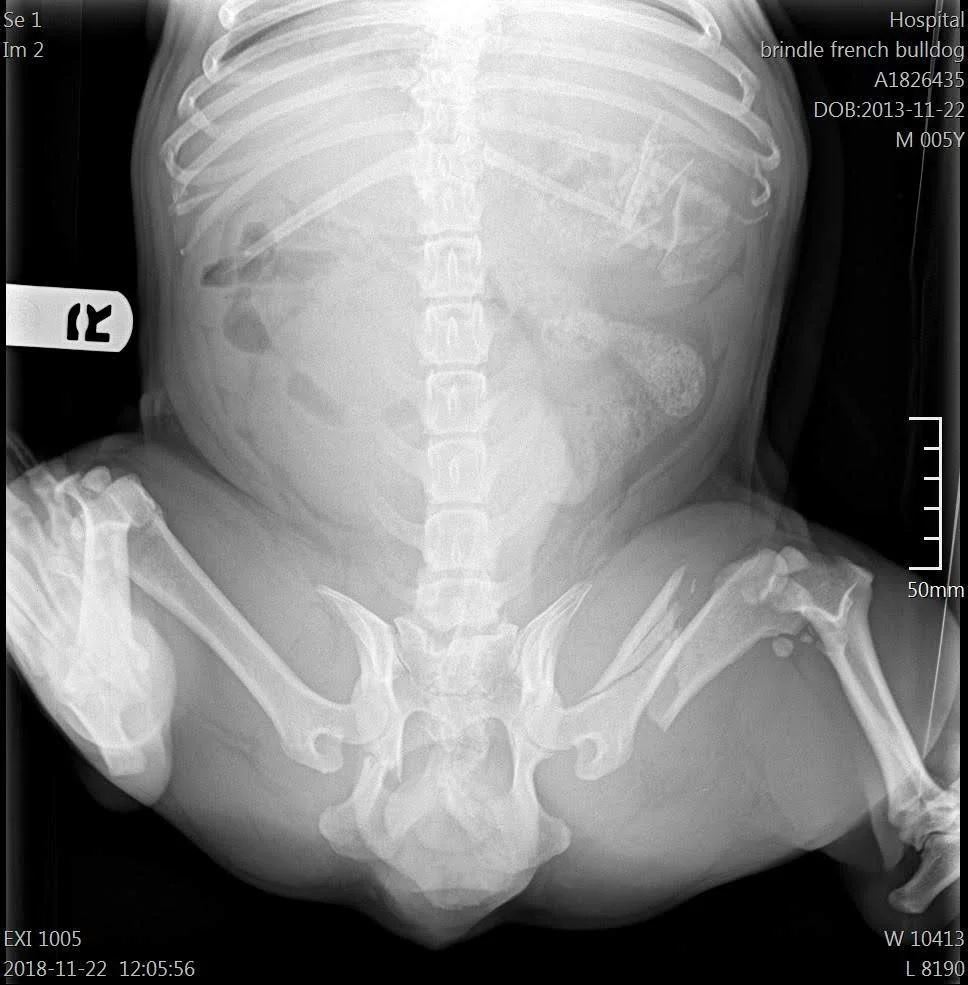

CLIFF aka “Big Red”, Old Hip Injury

Cliff, or "Big Red", as they called him, was the longest shelter resident and after his 5th call out, was out of time. The next day, X-rays found that Cliff has a nearly exploded hip socket from what is suspected to be a big impact injury, an old injury. It’s likely he had been hit by a car and been living with fragments grinding bone-to-bone for years. Despite his unimaginable pain, Cliff has been the most pleasant, eager-to-please guy giving big tail wags and smiles to just about anyone. After months of recovery, rehabilitation including physical therapy, acupuncture, water treadmill, Cliff is healed and home.